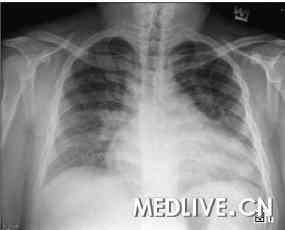

患者入院后胸部X线检查(图1)显示心脏肥大,心脏胸廓比为0.62,肺纹理增粗明显。心电图检查提示,有不完全性右束支传导阻滞,右心房与左心房肥大。

图1

胸部X光显示,心脏肥大及两侧肺血管充血